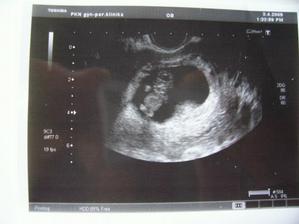

Nová naděje. Bohužel to bylo opět stejné, jako již dvakrát předtím. Třetí revize, třetí ztráta naděje. Jsem po laparoskopii a hysteroskopii a čekáme na výsledky imunologie v Plzni. Pak se uvidí co dál. V únoru 2009 nám v Sanusu doporučili ještě dva měsíce domácího snažení. Tak jsme se snažili a nyní napjatě sledujeme čárku. HCG nám krásně stoupá, 20. den po ovulaci je 2066. Máme 1. fotku dutinky. Přes nejrůznější potíže a patnáctidenní hospitalizaci nám miminko krásně roste. 22. dubna konečně po čtrnácti dnech ukázalo nosánek, máme nosní kůstku, NT je 2,0. Máme vše, co máme mít a rodiče se dnes poprvé společně dívali na ultrazvuk. Viděli mě i 4D, to koukali. Odnesli si video a teď na něj pořád koukají. Další kontrola náš čeká 5. května, opět ultrazvuk, triple testy a poradna. Trošku změna situace, mamka se mnou leží od 27. dubna v nemocnici, ale já ji dělám radost, rostu, 16.6. už vážím 360 gramů a od 5.6. ji kopu a ona o tom ví. Od 10. 6. se nám začal malinko měnit nález až jsme museli 10. 7., gr. h. 24+2 na cerclage, potom jsme měli zánět ledvin a astmatický záchvat. Pořád mamce tvrdlo břicho, tak se bez infuzí neobejde. 18. 7. se ještě objevilo krvácení, ale nebylo to nic závažného, byli jsme na ultrazvuku a vážím 908 gramů. V pátek 24.7. se to zlepšilo a kapeme na nejnižší rychlost, hurá. Mamka zatím nesmí chodit, má to slíbeno na 2. září. Kapeme sice na nejvyšší rychlosti, ale na ultrazvuku 4.8. mám odhad 1280 gramů. Dne 18.8. jsme byli na ultrazvuku a mám odhad 1750 gramů, mám trochu víc plodové vody a tak si tam plavu jako v bazénku. Dne 28.8. jsme byli s mamkou zase na ultrazvuku, vážím už 1950 gramů, mám udělaný krásný 3D fotečky, vody už nemám tolik moc, tak je mamka ráda. Jen se nám zase zkrátil čípek, už mě tam drží jen steh a 13 mm, ale držím mamce pěstičky, aby jsme vydrželi. No a taky si musím zvykat, mamka totiž má už dovoleno chodit na wc, a já jsem byl zvyklej, že pořád leží. Je sice z toho unavená, ale šťastná. Já jsem jí ještě udělal radost, že jsem se přetočil hlavičkou dolů. Dne 1.9. se mi konečně podařilo zbavit se té nitě, co tam mamka měla. Všichni jsou překvapení, jak se to mohlo stát, ale steh je pryč. Dne 10. 9. jsme s mamkou byli zase na ultrazvuku, vážím 2368 gramů (33+1). Hrdlo máme sice jen 9 mm, ale já se tam ještě udržím! Plodové vody mám už akorát, mamce klesly jaterní testy, žlučové kyseliny jsou v normě, tak má radost. Tak dnes 17. 9. jsem se byl zase vážit, mám 2517 gramů. Hrdlo má mamka jen 6,7 mm s obrovitým funnelingem, ale pořád drží. Denně mi točí monitory, mám je vzorné a pořád nemůžu přijít na to, jak ty sondy odkopnout. 26.9. pustil pan doktor mamku na propustku, byla poprvé 12 hodin mimo nemocnici, byli jsme na zahradě, grilovali jsme a já jsem babičce, dědečkovi a strejdovi předváděl, jak umím krásně kopat. Mamka byla moc šťastná. Večer se vrátila do nemocnice, dala si po 23. hodině sprchu a když usínala, tak jsem ji hodně překvapil, vypustil jsem svůj bazén. A tak se nešlo spinkat, ale na porodní sál. Šlo to pěkně a přesně ve 4.00 hodin jsem se narodil za skvělé asistence mého tatínka, který mamince na sále moc pomáhal. Vážím 2740 gramů a měřím 50 cm. Dosáhl jsem gestačního stáří 35+4. Rodiče a velká spousta lidí kolem ze mě mají velikánskou radost. Trošku jsem odmítal v inkubátoru dýchat, tak mě 1 den pomáhal CPAP. Večer mi ho vzali a teď už se snažím sám. mamka za mnou chodí a já jsem rád, když ji vídím. Dnes jsem na ni poprvé otevřel očička, snažím se papat, dnes už ze stříkačky. Tatínek je ze mě unešenej a já jsem rád, když mě přijde pohladit a vyfotit.